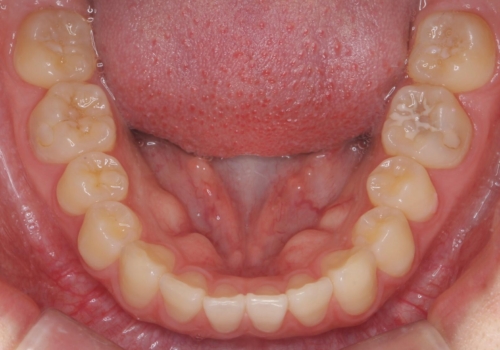

- 10代女性

- ワイヤー矯正

- 9ヶ月

- 前歯のすき間を気にして来院。

全体矯正ではなく部分矯正で治療することになりました。

その代わり、すき間をすべて閉じるのは難しく、両脇の目立たないところに集めて治療終了しています。

低予算、短期間で治療も終了し、大変満足していただきました。

全体矯正をしていないため、就寝時にリテーナー使用は継続していただくことになっています。